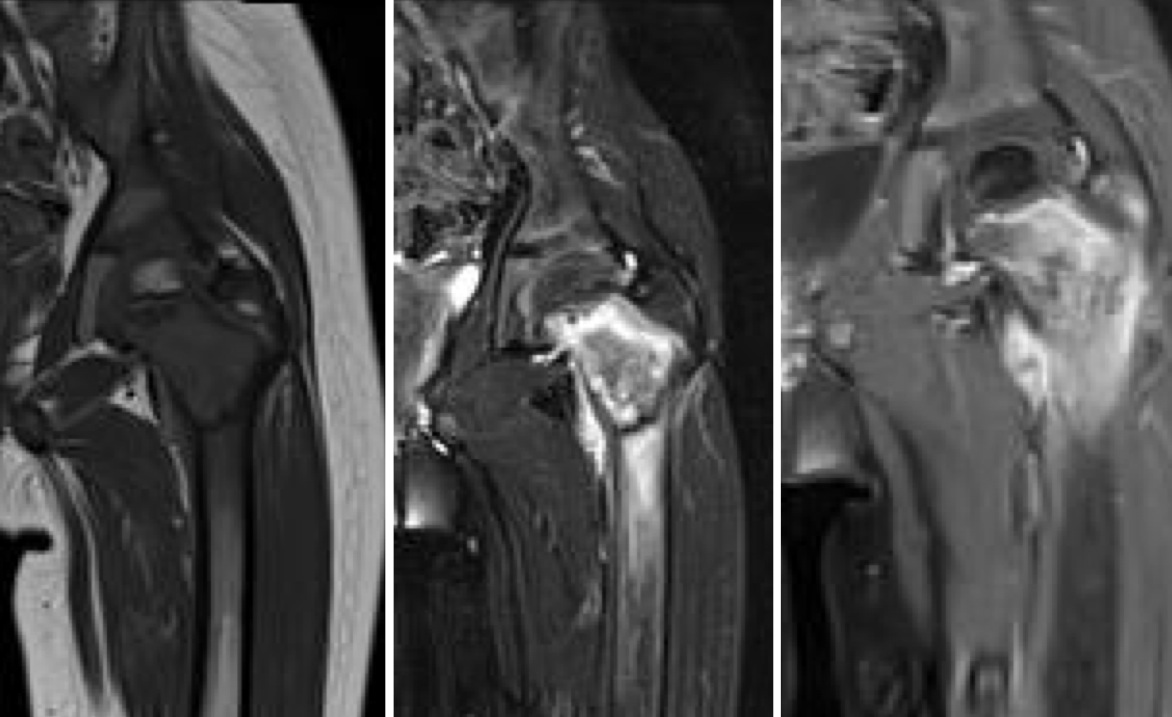

Figure 3 for case Langerhans cell histiocytosis ( RID3846 )

Figure 3